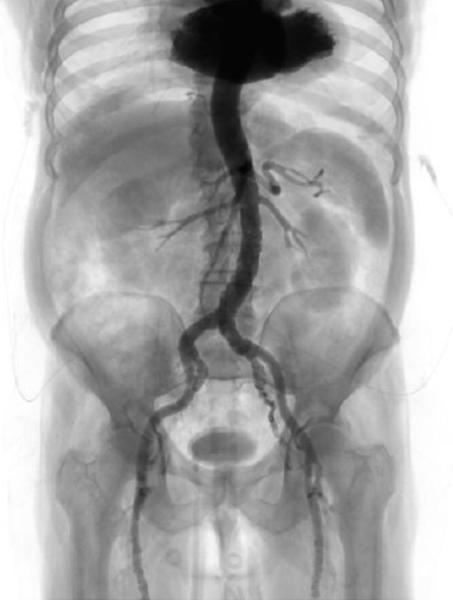

Case planning: CT

- Learn why and how cardiac CT is playing an increasingly important role in the evaluation of patients with severe aortic stenosis (e.g., calcium score, coronary evaluation)